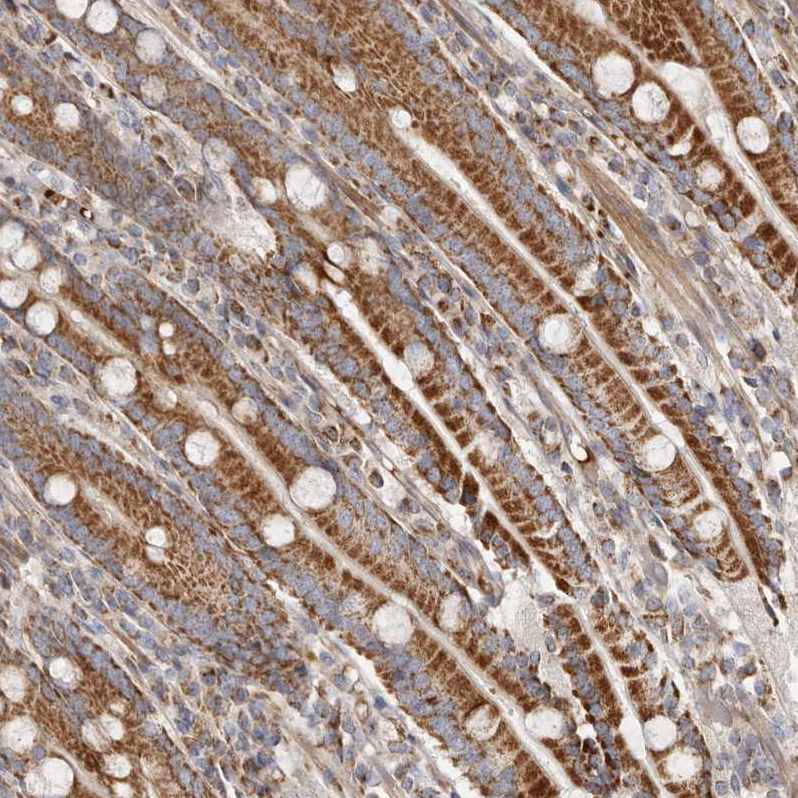

Immunohistochemical staining of human liver shows strong cytoplasmic positivity in hepatocytes.